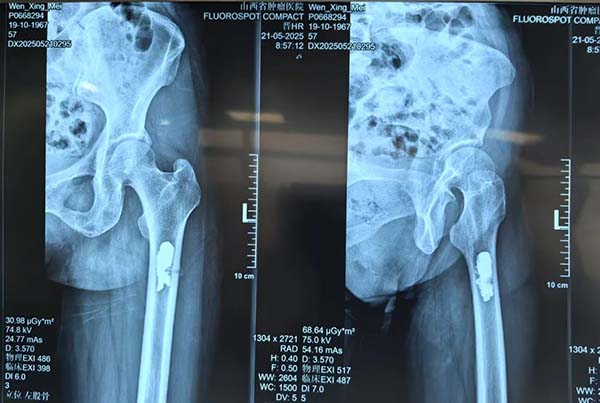

经多学科会诊(MDT),团队制定“微波消融+骨水泥填充”微创个性化方案。术中在C型臂精准引导下,直径仅2毫米的消融针直达肿瘤核心,通过高频微波产生100℃以上高温,实现肿瘤组织瞬间凝固性坏死,同时注入骨水泥强化骨骼支撑。术后复查X线显示消融范围覆盖病灶,骨水泥填充稳定。

术后复查X线